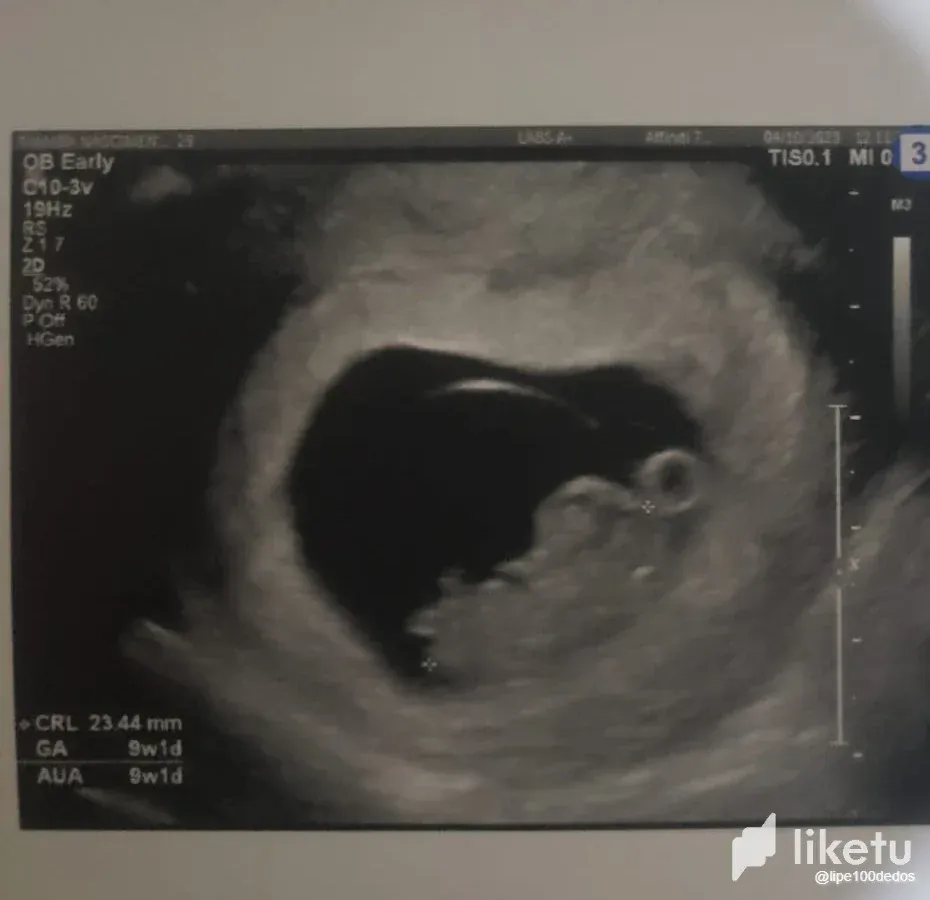

At first there was a mixture of happiness and worry. Due to private issues, I imagined that the pregnancy could be risky, mainly because Tamara had been feeling VERY unwell for a week, and it wasn't the normal unwell feeling of a pregnancy. At the time we decided not to talk about it publicly until we knew how the baby's health was and how the pregnancy was going. But that week we had our first ultrasound after several tests and the news came back that everything was fine! Everything was as expected. Tamara still feels sick, but she's been feeling sick for two weeks, just like in a normal pregnancy. We're still very early in the pregnancy, as you can see from the scans, we're in our 9th week and heading towards our 10th. But just knowing that everything is fine health-wise is already a relief and gives room for happiness.